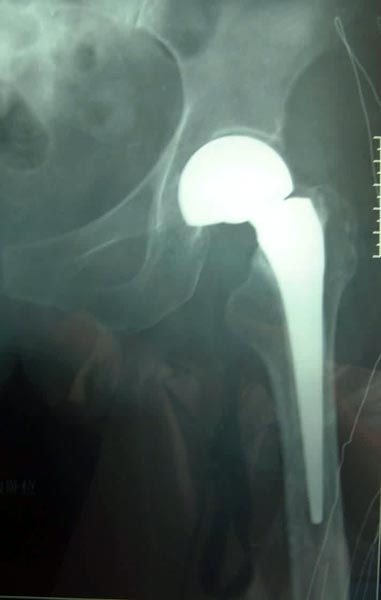

患者92岁,男性,股骨颈骨折,伴高血压、糖尿病、冠心病、骨质疏松。

采用小切口微创双极人工股骨头置换术置换术。

患者术后5天下地活动,恢复满意。